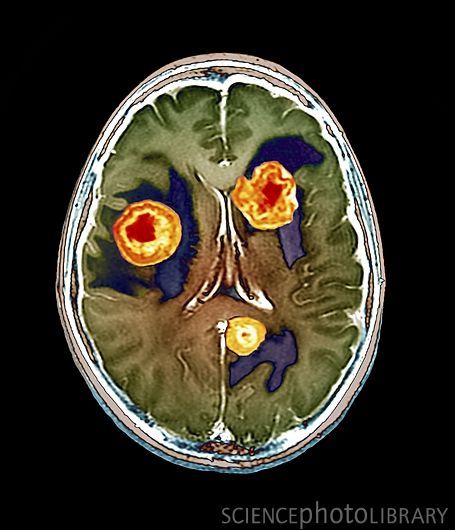

- При подозрении на опухоль нативная МР-томография выявляет первичный очаг, но для оценки структуры, размеров, обнаружения метастазов проводится внутривенное контрастирование;

- Опухоли и кисты;

Когда делают контрастную томографию мозга

Для дополнительной визуализации структур, которые не выявляются при нативной МРТ или КТ, проводят внутривенную инъекцию контрастного средства. После заполнения сосудов на томограммах прослеживаются сосуды, внутримозговые цистерны (при МРТ). Дополнительная томограмма головы с контрастным усилением позволяет выявить расширение внутримозговых желудочков, расслоение стенки артерий (аневризму), аномалии развития, разрывы сосудов, невротические стенозы, тромбофлебиты артерий (скопления сгустков крови).